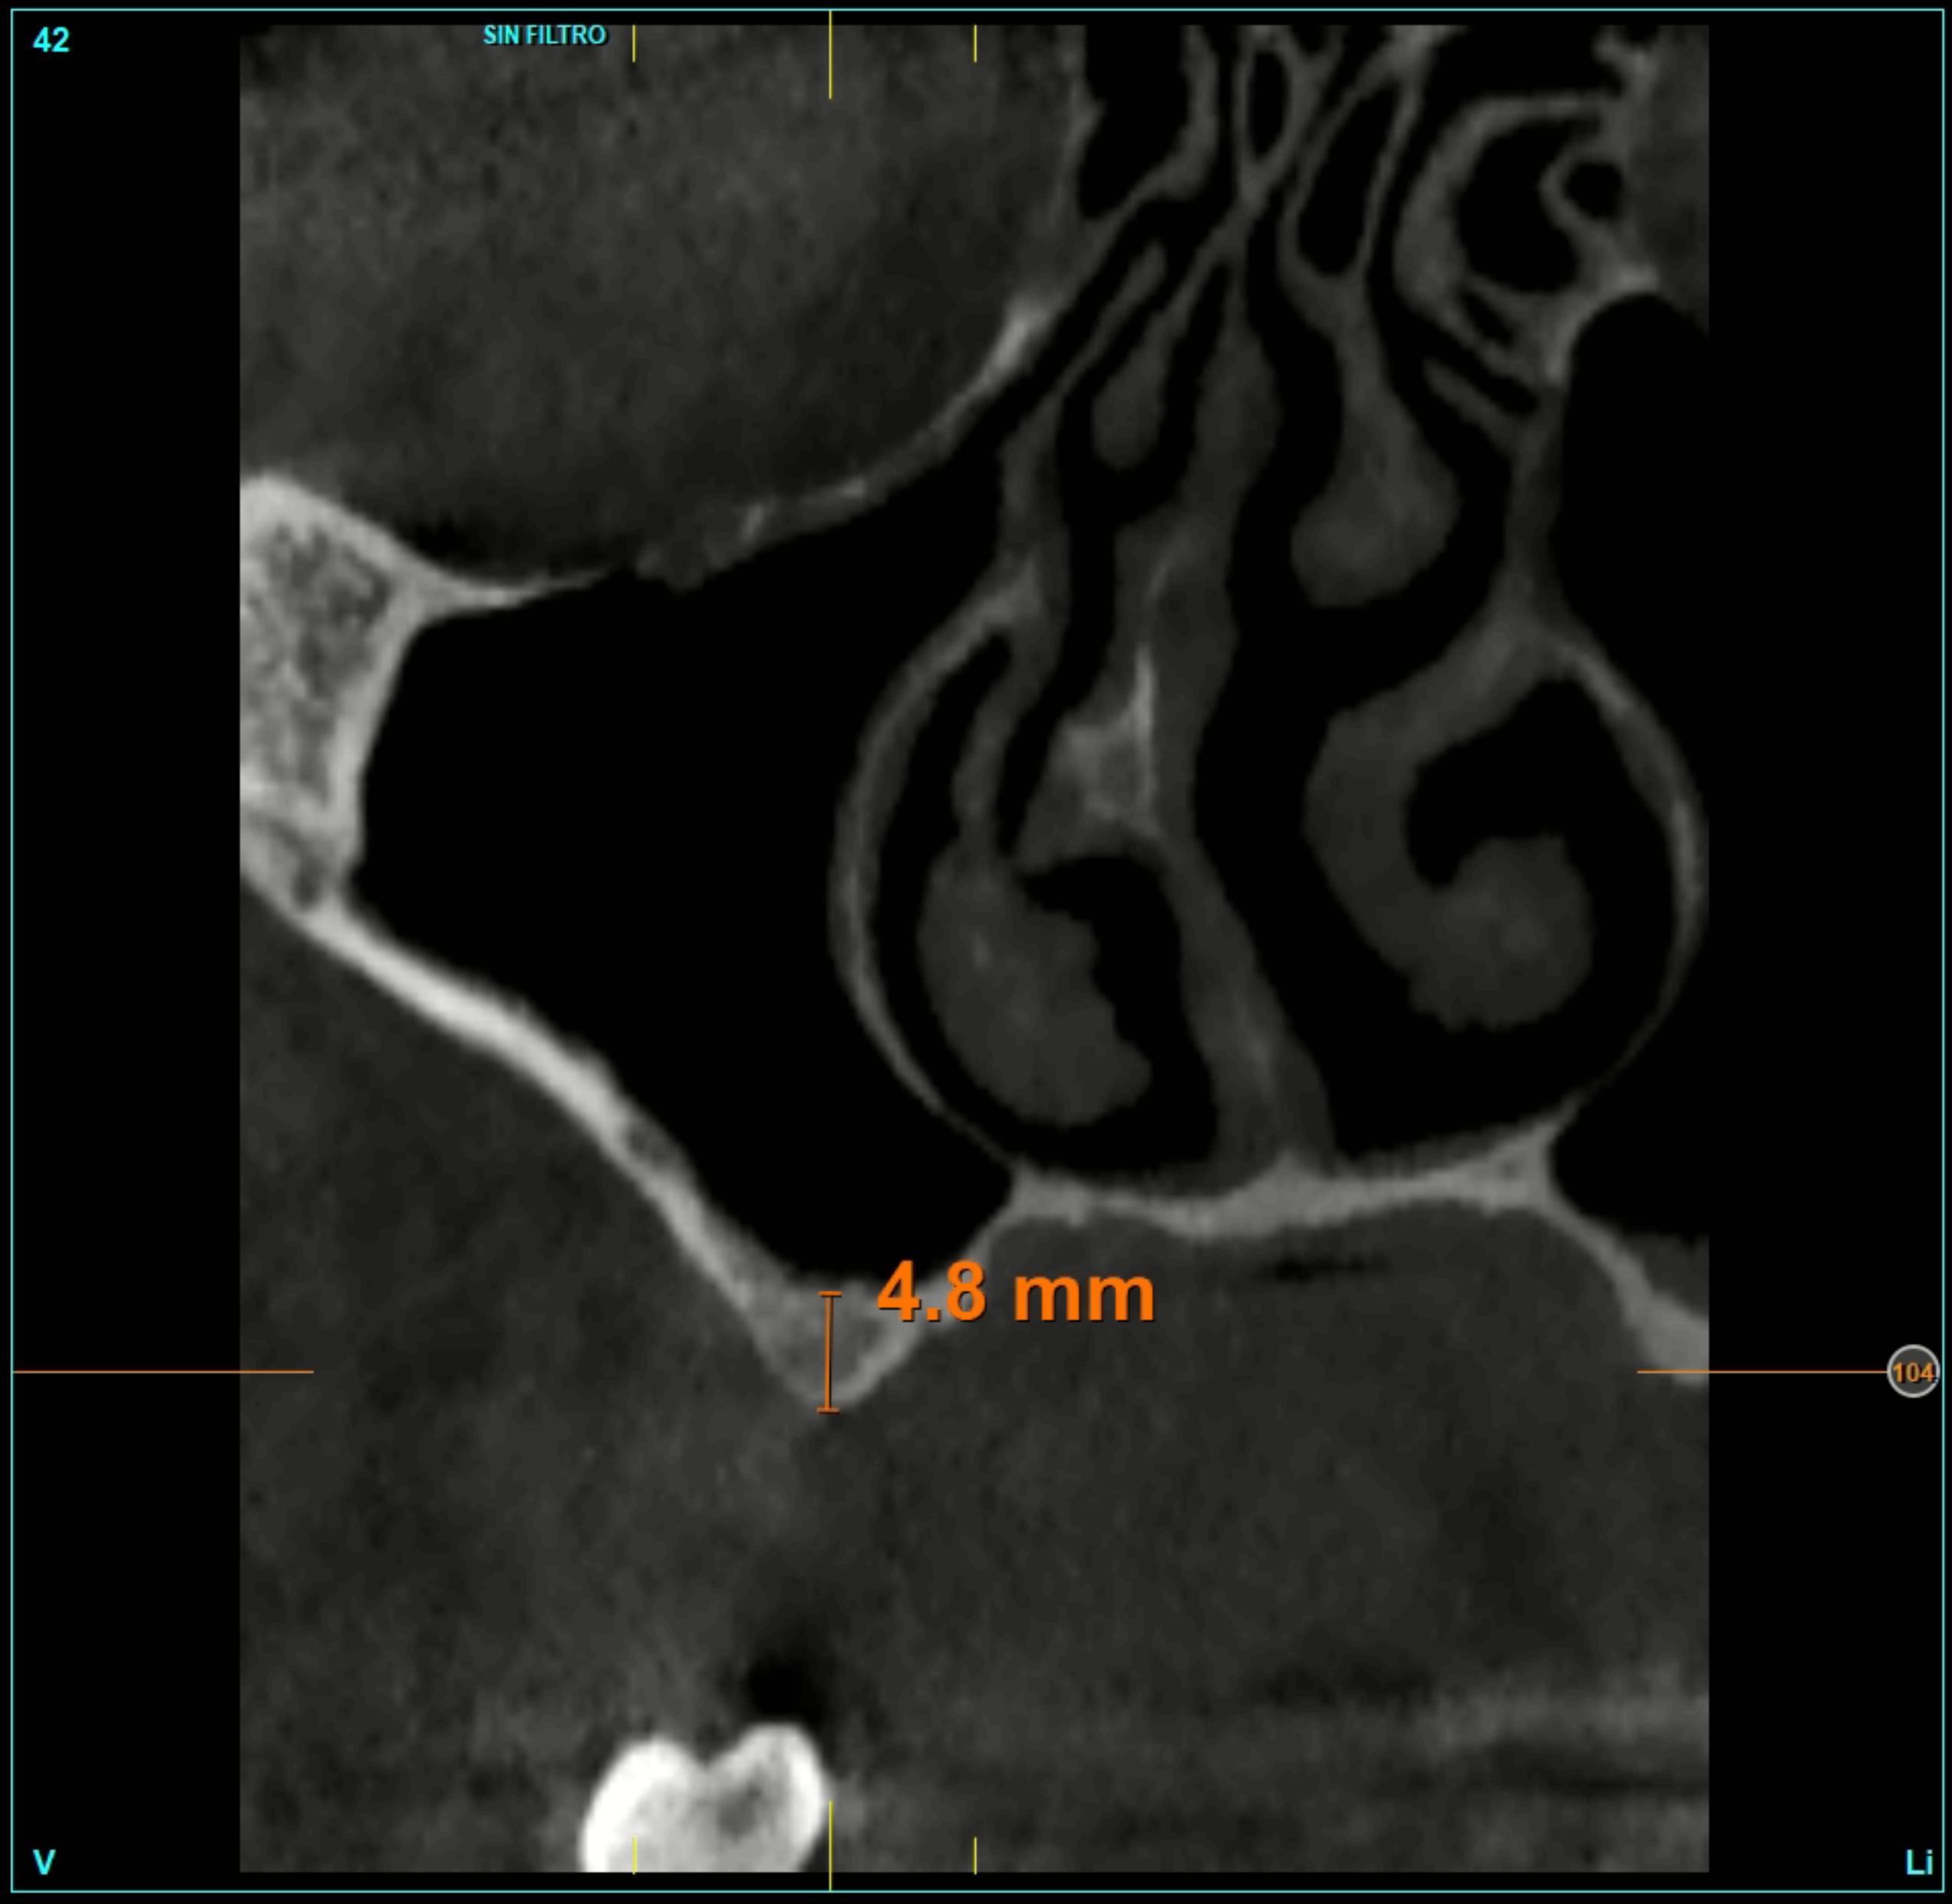

È stata effettuata una revisione retrospettiva di tutti i casi nei quali sono stati inseriti impianti di 4,5 mm di lunghezza sottoposti a protocollo di carico immediato. I trattamenti sono stati eseguiti in un’unica clinica di Vitoria (Spagna) negli anni 2020 e 2021. Nell’ambito dello studio preoperatorio, tutti i pazienti sono stati valutati mediante esame clinico, modelli diagnostici e CBCT (Cone Beam), successivamente analizzati con un software di pianificazione dedicato (BTI-Scan III). Al fine di definire con precisione la futura riabilitazione, è stato eseguito un ceraggio diagnostico dal quale è stata realizzata una guida chirurgica personalizzata.

L’altezza media della cresta ossea residua era di 5,11 ± 1,06 mm, mentre la densità ossea media nelle sedi implantari era di 566,67 ± 349,48 HU. Il torque medio di inserimento degli impianti è stato di 34,71 ± 18,25 Ncm. L’analisi del torque in funzione della posizione implantare e del tipo di osso ha evidenziato un comportamento biomeccanico coerente con la densità ossea attesa per ciascuna regione anatomica. Gli impianti inseriti in osso di tipo I e II hanno generalmente raggiunto valori di torque più elevati, frequentemente compresi tra 40 e 60 Ncm, soprattutto nelle regioni posteriori (26, 27, 36 e 37). Al contrario, negli impianti inseriti in osso di tipo III e IV, i valori di torque tendevano a essere inferiori e più dispersi, oscillando prevalentemente tra 20 e 40 Ncm. Nonostante ciò, anche nei siti con qualità ossea inferiore, i valori ottenuti rientravano in intervalli clinicamente accettabili per consentire la stabilità primaria necessaria ai protocolli di carico immediato adottati nello studio. Nel Grafico 3 è riportata la distribuzione del torque in base alla sede anatomica e al tipo di osso.

Al termine del follow-up, la perdita ossea crestale media è stata di 0,73 ± 0,18 mm in mesiale e di 0,85 ± 0,34 mm in distale. Alcuni casi clinici rappresentativi sono illustrati nelle Figure 2-10.